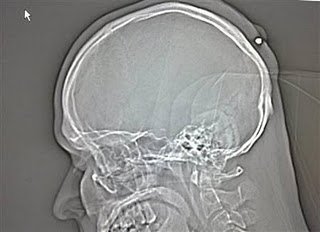

2. Peluru 5 tahun dalam kepala

Seorang pria yang hidup di Jerman hidup dengan normal dan baik-baik saja selama lima tahun tanpa menyadari ia telah ditembak di kepala. Peluru kaliber 0,22 ditemukan ketika orang itu pergi ke dokter untuk memiliki apa yang ia pikir merupakan kista . Yang dia ingat adalah bahwa ia telah menerima pukulan ke kepala sekitar tengah malam di sebuah pesta Tahun Baru tahun 2004 tapi sudah lupa tentang hal itu karena ia �sangat mabuk.�